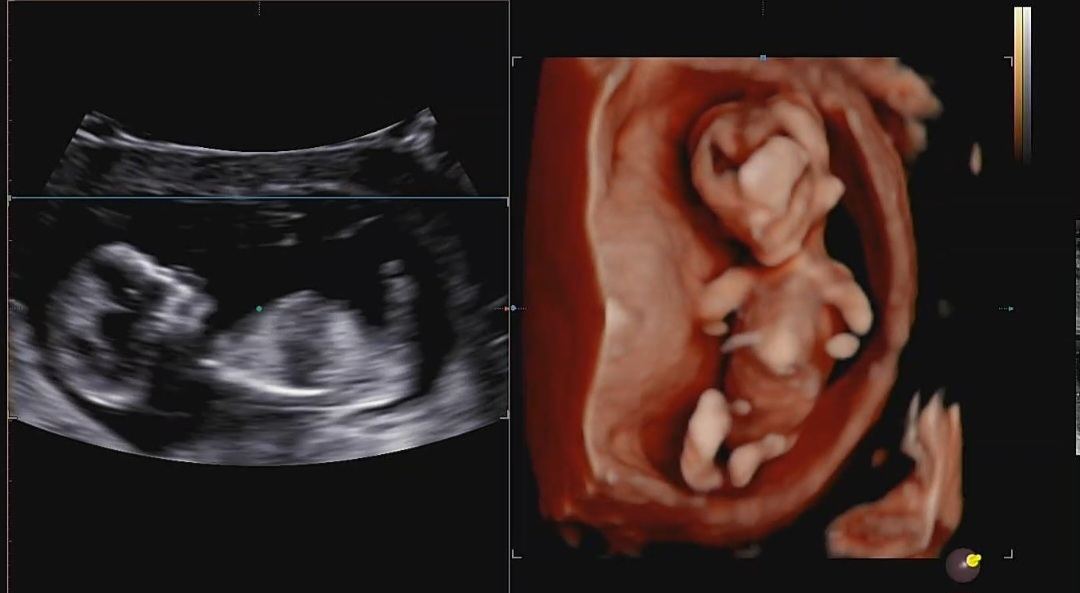

12주1일차 병원 다녀왔어용~ 각도법 어떻게 보이시나요?! 50%이상 확율로 엄마 닮았을거 같다는데...... 안심해도 될까용ㅎ 참견 부탁드려요 !!!

입초로는 모르구요 왼쪽 촘파는 성기안보여서 각도법 못봐요!